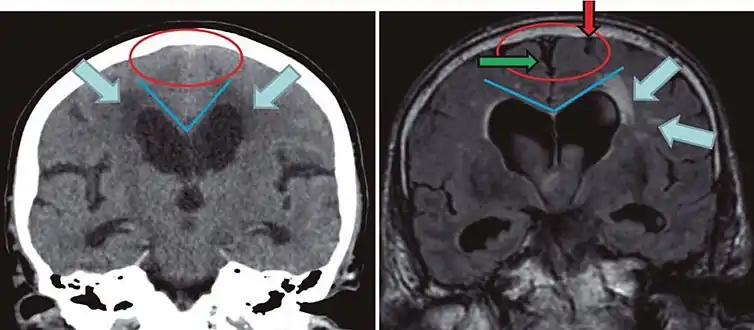

- Imaging from magnetic resonance imaging (MRI) or computed tomography (CT) is needed to demonstrate enlarged ventricles and no macroscopic obstruction to cerebrospinal fluid flow. Imaging should show an enlargement to at least one of the temporal horns of lateral ventricles, and impingement against the falx cerebri resulting in a callosal angle ≤ 90° on the coronal view, showing evidence of altered brain water content, or normal active flow (which is referred to as "flow void") at the cerebral aqueduct and fourth ventricle.

| Normal pressure hydrocephalus | Brain atrophy | |

|---|---|---|

| Preferable projection | Coronal plane at the level of the posterior commissure of the brain. | |

| Modality in this example | CT | MRI |

| CSF spaces over the convexity near the vertex (red ellipse | Narrowed convexity ("tight convexity") as well as medial cisterns | Widened vertex (red arrow) and medial cisterns (green arrow) |

| Callosal angle (blue V) | Acute angle | Obtuse angle |

| Most likely cause of leucoaraiosis (periventricular signal alterations, blue arrows |

Transependymal cerebrospinal fluid diapedesis | Vascular encephalopathy, in this case suggested by unilateral occurrence |

MRI scans are preferred. The distinction between normal and enlarged ventricular size by cerebral atrophy is difficult to ascertain. Up to 80% of cases are unrecognized and untreated due to difficulty of diagnosis.[7] Imaging should also reveal the absence of any cerebral mass lesions or any signs of obstructions. Although all patients with NPH have enlarged ventricles, not all elderly patients with enlarged ventricles have primary NPH. Cerebral atrophy can cause enlarged ventricles, as well, and is referred to as hydrocephalus ex vacuo.